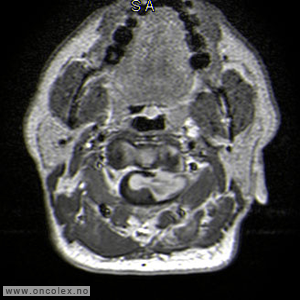

MR er det viktigste diagnostiske hjelpemiddel for å påvise svulst i ryggmargen, ryggmargsnervene og ryggmargshinnene. CT kan også brukes, men har klare begrensninger når det gjelder fremstilling av svulstene. Blant annet kan svulster som ikke tar opp kontrast bli oversett. CT og skjelettrøntgen kan imidlertid være nyttig for å kartlegge grad av skjelettødeleggelse og eventuell instabilitet i ryggsøylen.

Bildeeksempler